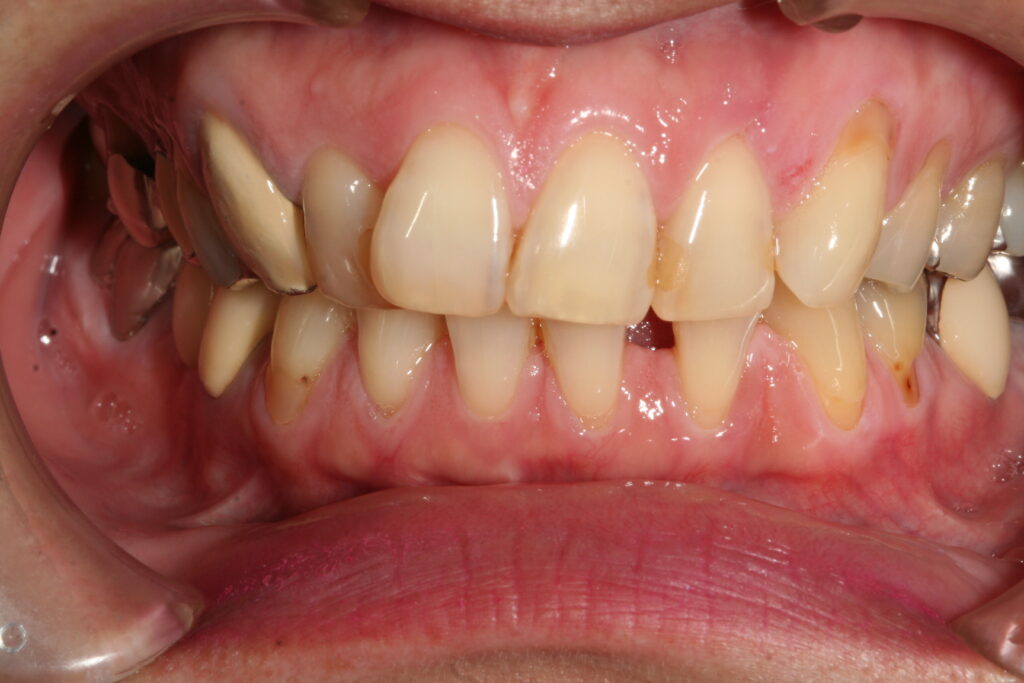

審美歯科 2018.07.24 症例紹介 45歳女性下の前歯の隙間が気になるということで来院。一本だけ治療し、ポーセレンラミネートべニアで審美治療を行いました。治療回数は2回です。 症例紹介 審美 歯科 佐賀前の記事 お盆の休診日次の記事